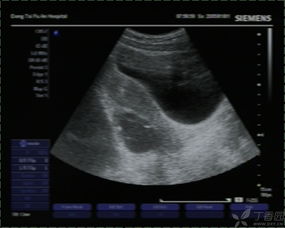

常規(guī)B超檢查是不需要空腹的,因?yàn)樗皇芟罋怏w的影響,常規(guī)B超檢查主要是通過B超的探測頭在腹部進(jìn)行探測,從而檢查女性的子宮以及盆腔部位。并且懷孕的女性做B超,一般也是做常規(guī)B超檢查,而不是采取陰道B超檢查,因?yàn)槟軌蜃畲蟮谋Wo(hù)胎兒。

做常規(guī)B超檢查需要注意的一個(gè)地方,就是最好在B超檢查時(shí)能夠補(bǔ)充大量的水分,讓膀胱充盈起來,這樣才能讓結(jié)果更加的準(zhǔn)確和清晰。早孕的女性需要補(bǔ)充水分,孕13周以后的女性在做常規(guī)B超檢查的時(shí)候就不需要喝水,讓膀胱充盈了。

肝膽胰等部位的B超檢查需要空腹,因?yàn)楦文懸任挥谂枨桓共康纳钐?,因此也就特別容易受到消化道氣體的影響,如果不空腹去進(jìn)行檢查就非常容易使結(jié)果產(chǎn)生偏差,從而達(dá)不到檢查的目的。

做B超檢查的時(shí)候是否空腹,主要是看具體是針對(duì)哪一部位的B超檢查,要具體情況具體分析。如果不知道自己做的B超檢查是否要空腹,需要提前就咨詢醫(yī)生,以免耽誤檢查的時(shí)間。